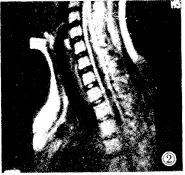

短頸畸形2.屈伸拉動力性頸椎側位片,融合椎體節段失去正常頸椎的圓滑曲線,椎間隙不發生變化。

3.短頸畸形在X線正側位片上很難清楚地顯示畸形部位,表現有以下幾點特徵:

①頸椎兩個或兩個以上椎體和附屬檔案的部分或全部融合。

②一個或多個椎間隙消失或部分消失。

③椎體扁而寬,有時為半椎體畸形。

④融合椎體的鄰近頸椎節段增生、退變。椎管矢狀徑減小形成椎管狹窄。